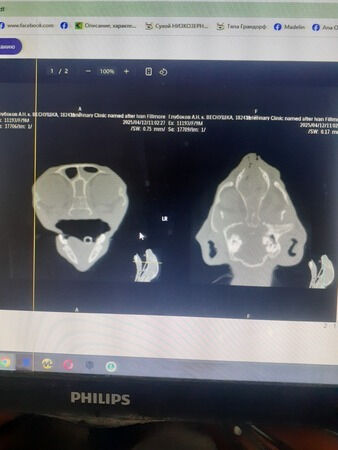

Vor ein paar Tagen haben wir eine zweite kleine Katze namens Vesnushka operiert. Wir haben sie am 19. September letzten Jahres in der Nähe des Zauns unserer Nachbarin Natalia aufgelesen, die sich gerade mit ihrer Freundin unterhielt und das Kätzchen nicht sah. Und das kleine Kätzchen, das etwa einen Monat alt war, sass still im Gras, ohne dass sie es sah. Und als sie es sah, war sie schockiert, aber sie weigerte sich, es aufzunehmen (ihre eigenen Katzen + schlechte Gesundheit + familiäre Umstände). Sie versuchte immer wieder, die Katze zu finden, die dieses Baby zur Welt gebracht hatte, und eines Tages, als sie zwei unbekannte graue Katzen auf ihrem Grundstück sah, rief sie mich an und schrie ins Telefon: „Margarita, komm schnell, ich habe die Eltern dieses Kätzchens gefunden!“ Ich eilte zu Natalias Garten und sah dort... meine alte Katze Agafya und einen jungen Kater Boris, natürlich kastriert)). Später fanden wir noch heraus, dass jemand, der eine Katze hatte, die Kätzchen zur Welt gebracht hatte, sie einfach an verschiedenen Orten aussetzte. Wir hatten Glück, denn eine andere Nachbarin hatte 3 Kätzchen an ihren Zaun geworfen bekommen! Aber sie nahm sie Gott sei Dank alle auf.Die Gesundheit unseres kleinen Mädchens erwies sich als zerbrechlich, und solange sie bei uns lebt, solange wir sie behandeln, aber die Behandlung half nur eine Zeit lang. Als die Medikamente nach einer Weile abgesetzt wurden, ging es ihr immer schlechter.Wir mussten eine Operation durchführen - CT + Rhinoskopie - und haben auch viele verschiedene Untersuchungen gemacht.Was zeigte der CT-Scan? Parodontitis, Rhinosinusitis, Otitis externa und Otitis media beidseitig, Polype im linken äußeren Gehörgang, Frontitis, Lymphadenopathie. Bakteriologische Kulturen ergaben Staphylokokken und Streptokokken, andere Tests zeigten Kalzivirose und Mykoplasmose. Uns wurde ein geeignetes Medikament verschrieben und wir setzen die Behandlung fort....Die Klinik gewährte uns als Tierheim einen Rabatt von 50 % und wir zahlten nur 250 Euro, aber selbst dieser Betrag ist für uns sehr hoch, da wir viele Tiere in unserer Obhut haben.